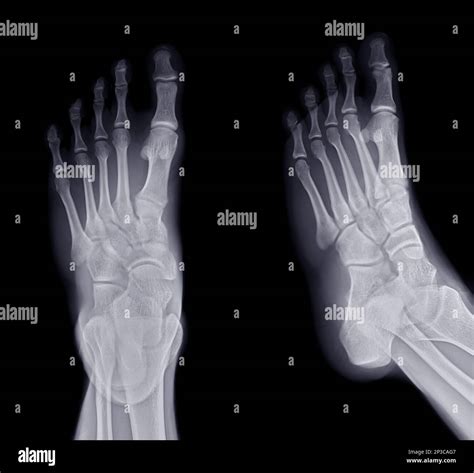

The patient is positioned on the X-ray table, and the foot is placed in a specific position to capture the desired views. Common views include:

• Anteroposterior (AP) view: Shows the foot from the front.

• Lateral view: Shows the side of the foot.

• Oblique view: Shows the foot at an angle.

Interpreting a Normal Foot X Ray involves a thorough examination of the images to ensure that all structures appear normal. Key areas of focus include:

Bones

The bones of the foot, including the tarsals, metatarsals, and phalanges, should be clearly visible and aligned properly. Any fractures, dislocations, or deformities would be immediately apparent.

Joints

The joints between the bones should be smooth and well-defined. Any signs of arthritis, such as bone spurs or joint space narrowing, would indicate an abnormality.